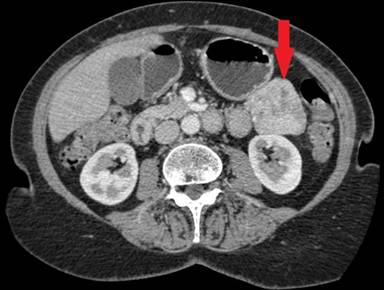

A 62-year-old lady presented to the dermatology clinic with a 36-month history of dermatosis affecting the lower legs, axillae, groins and sub-mammary regions (Figures 1 and 2). The rash was intermittent in nature, non-pruritic, associated with hair thinning, and had not responded to topical treatments. Skin patch testing was negative and therefore skin biopsies were taken. These biopsies showed necrolytic migratory erythema. Blood tests were ordered to include minerals and electrolytes, chromogranin A and glucagon levels. Zinc levels were found to be low, N-terminal glucagon raised at 965 ng/L (reference range: 0-250 ng/L) and c-terminal glucagon raised at 580 ng/L (reference range: 0-150 ng/L). The biochemical diagnosis of a pancreatic glucagonoma was confirmed and cross-sectional imaging demonstrated a 5 cm mass lesion in the body and tail of the pancreas with no evidence of nodal disease or other metastatic spread (Figure 3).

Figure 3. Cross sectional CT scanning showing a mass in the tail of the pancreas (red arrow). |

Five years after laparoscopic distal pancreatosplenectomy, surveillance glucagon levels showed a slight elevation whilst the patient remained otherwise well and asymptomatic. CT scanning showed a suspicious lesion in the distal small bowel, deep in the pelvis, with mucosal thickening and hyper-enhancement. This was thought to be a primary neuroendocrine tumour of the small bowel (Figure 4), as this would be regarded as an unusual site for recurrence of a primary pancreatic NET.

Figure 4. Cross sectional CT scanning demonstrating an abnormality in the pelvis, thought to be dilated terminal ileum with mucosal thickening and hyper-enhancement (red arrow). |